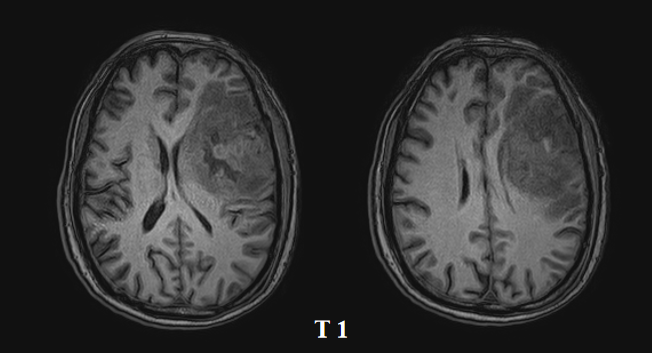

胶质母细胞瘤四级

多形性胶质母细胞瘤

胶质母细胞瘤